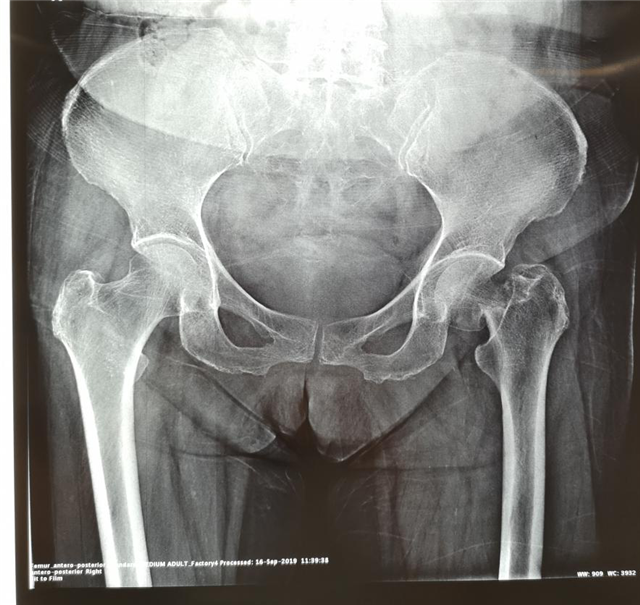

治疗前

陈女士1年前因左股骨颈骨折在创伤骨科与手外科住院,并由陈跃平主任主刀完成左人工全髋关节置换术,术后恢复效果佳,不久后便痊愈出院,关节功能恢复良好。后来,陈女士姐姐同样因为外伤导致了左股骨颈骨折,受伤后在当地医院住院治疗,当陈女士得知姐姐病情后,毫不犹豫地推荐她转到广西中医药大学附属瑞康医院创伤骨科与手外科进行治疗,并一再强调让龙飞攀医生主管。她经常把陈主任和龙医生挂在嘴边:"陈主任和龙医生真是很好,不但手术做得好,人也很随和,完全不把我们当病人看待,就像亲人一样。"